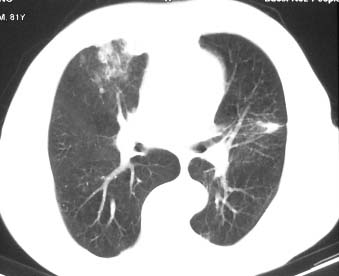

右肺上叶肿块,其远侧段肺组织炎性渗出性改变,局部胸膜粘连,肺门侧边缘光滑锐利,可见结节样病灶;右肺尖纤维索条状影,局部肺纹理纠集,纵隔窗窗宽不合适,病灶内部情况显示不清,未见明显淋巴结肿大及钙化.

考虑:1.右肺上叶周围性肺癌并肺内转移;2.右肺尖陈旧性结核.3.左肺炎性病灶.

右肺中叶软组织块(挑剔一下纵隔窗窗宽不理想),其周围可见多个类圆形结节,右肺上叶尖段见斑片、索条状致影,左肺小结节。

1.右肺周围型肺癌伴肺内转移;

2.右肺上叶陈旧性结核;

3.左肺炎性结节;

右肺中叶软组织块,其周围可见多个类圆形结节,右肺上叶尖段见斑片、索条状致影,左肺小结节,见分叶、毛刺及胸膜凹陷征。1.左肺周围型肺癌伴右肺内转移; 2.右肺上叶陈旧性结核。

老年人,适用多元论,考虑 :1、左肺周围型肺癌伴右肺内转移; 2、右肺上叶陈旧性结核。